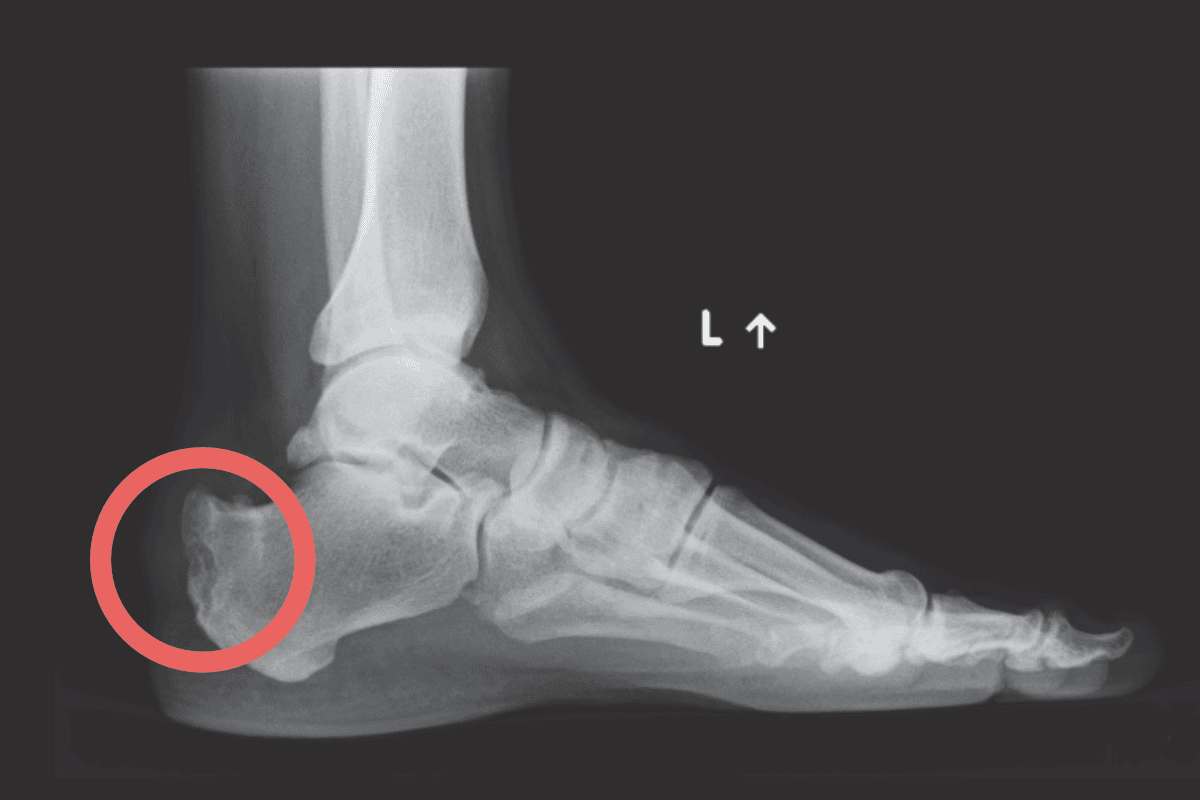

Pięta Haglunda to dokuczliwa zmiana polegająca na uwypukleniu guza kości piętowej, która prowadzi do przewlekłego podrażnienia tkanek miękkich, zwłaszcza kaletki głębokiej ścięgna Achillesa a następnie do stopniowego uszkadzania samego ścięgna. Stan ten jest częstą przyczyną bólu pięty, szczególnie u osób aktywnych fizycznie. Długotrwałe tarcie i ucisk pomiędzy zmienioną patologicznie piętą a obuwiem prowadzą do stanu zapalnego i przewlekłych dolegliwości bólowych wraz z ograniczeniem sprawności ruchowej.

- obrzęku i włóknienia tkanek miękkich otaczających guz piętowy oraz powstawania charakterystycznych zwapnień i “ostróg”,

- plastyka guza piętowego – najczęściej endoskopowa, ma na celu usunięcie konfliktującego fragmentu guza piętowego tak by zatrzymać uszkadzanie ścięgna Achillesa;